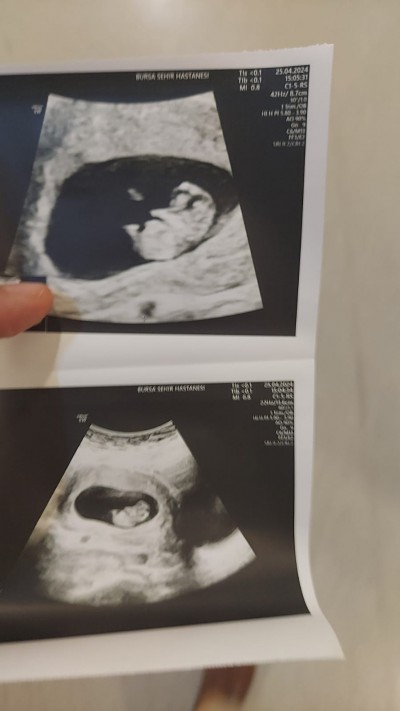

13 haftalik.

Üstteki ultrason en fazla 9 haftalik falandır alttakinde 14 hafta yazıyor ama 13  hafta demişsin. Altta ki ultrason için söylüyorum erkeğe benziyor